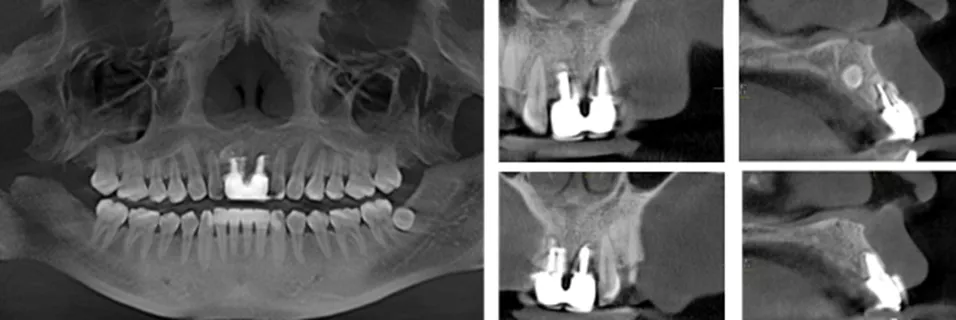

·      #11根中至根尖1/3折裂,桩核无断裂影像。根长7-8mm。根方牙槽骨偏腭侧埋伏近远中向多生牙。

·      #21腭侧根中/3折裂,牙周膜增宽,桩核无断裂影像。根长7-8mm,冠根比不足。

术后影像学检查